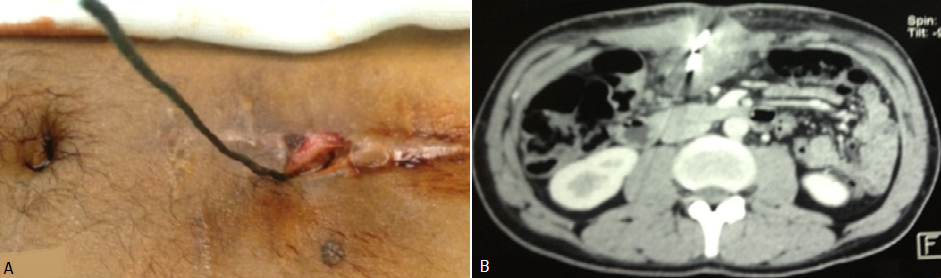

L'ingestion d'un corps étranger (CE) est une urgence médicale courante. Chez l'adulte, cet accident est beaucoup plus rare que chez l'enfant et survient le plus souvent sur des terrains prédisposés. Nous rapportons le cas d’un patient âgé de 36 ans, suivi en psychiatrie, admis en urgence pour l’ingestion d’un fil de fer faisant 15 cm de long et qui a été spontanément expulsé à travers la paroi abdominale au niveau de l’épigastre.L’examen clinique était sans anomalie notamment pas de signe péritonéaux (A). La tomodensitométrie abdominale (B) avait mis en évidence un corps étranger linéaire extériorisé depuis l’antre gastrique à travers un trajet fistuleux gastro cutané. Le fil de fer a été retiré sous anesthésie générale par une traction douce extériorisant le bout restant dans l’antre laissant une fistule gastro cutané qui n’a rien ramené.Les suites opératoires étaient simples. L’ingestion de CE est un problème fréquent en pratique courante. Près de 80% des CE ingérés traversent spontanément la filière digestive sans aucune complication. Dix à 20% nécessitent la réalisation d’une extraction endoscopique et moins de 1% une intervention chirurgicale. L’expulsion spontanée à traves la paroi abdominale reste un événement exceptionnel.